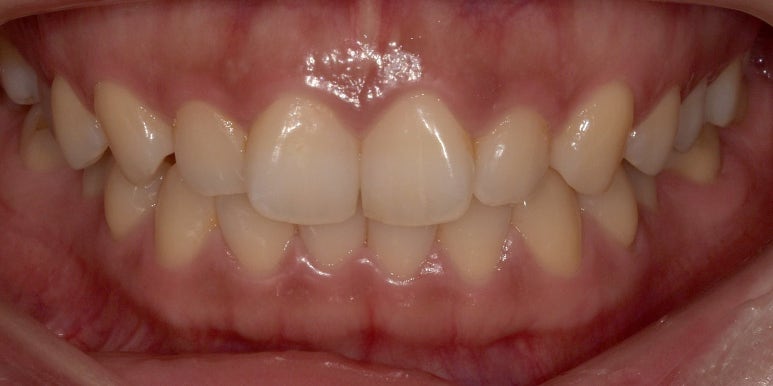

본격적으로 말씀드리기 전에 제 시술 전 치아 사진을 먼저 공개하겠습니다.

라미네이트 치료 전 모습입니다.

촬영일자: 2023-05-10

이렇게 사진을 놓고 보니까 괜히 굉장히 부끄럽네요… ㅠㅠ

저의 평소 고민은 앞니 2개가 약간 틀어진 나비치아라서 배열이 고르지 못한 점이었어요.